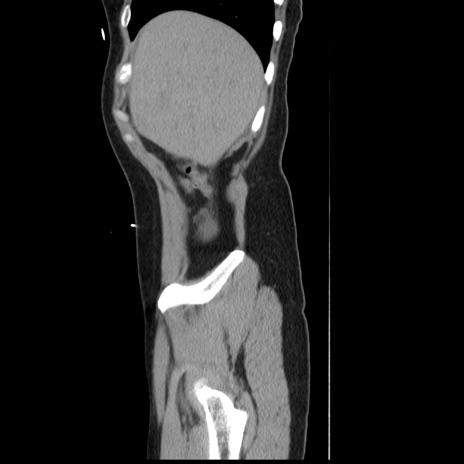

横断像

【症例】 50歳代女性

【主訴】 腹痛

【現病歴】前日生レバーを食べた。今朝に排便あり。 昼前に突然発症の腹痛を生じ、当院救急外来を受診した。

【既往歴】 子宮筋腫にてで子宮全摘後

【身体所見】 意識清明、腹部:平坦、軟、下腹部やや左を中心に圧痛・反跳痛あり、筋性防御あり

【データ】WBC 7800、CRP 0.07